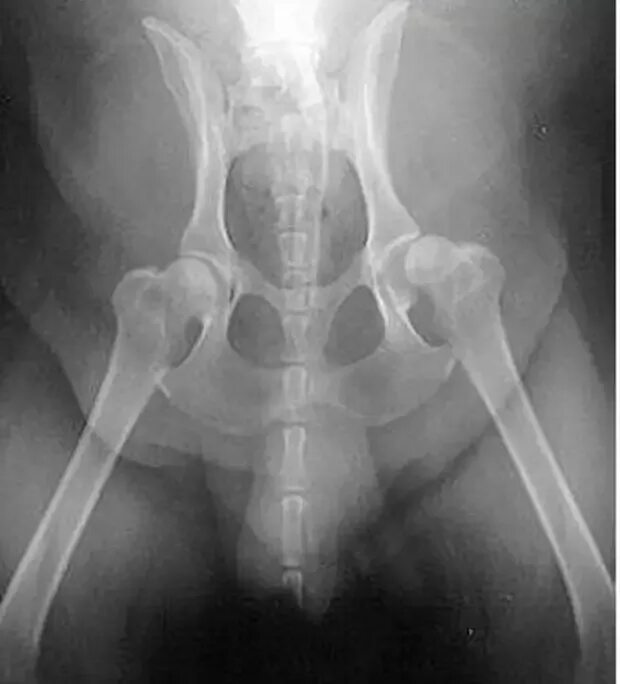

Деформация тазобедренного